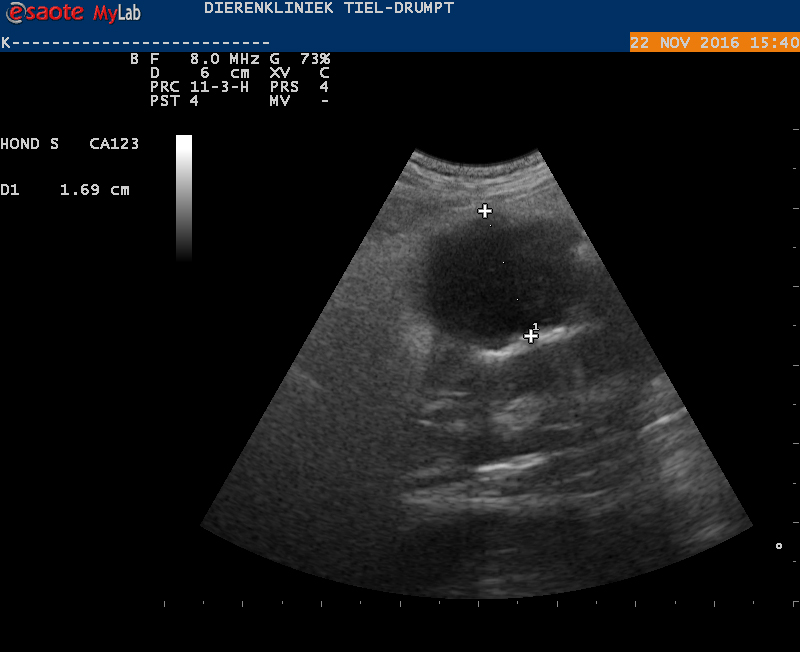

Om te weten wat er mis was, werd besloten een echo te maken.

Met de echo werden een aantal afwijkingen gezien. De belangrijkste waren een lokaal gebied van ontsteking en net boven een groot bloedvat was er een onregelmatig stuk darm te zien met een verdikte wand. Door alle veranderingen was niet goed te bepalen wat deze structuur exact was. Gezien het beeld en de leeftijd was de kans groot dat er sprake was van een tumor.